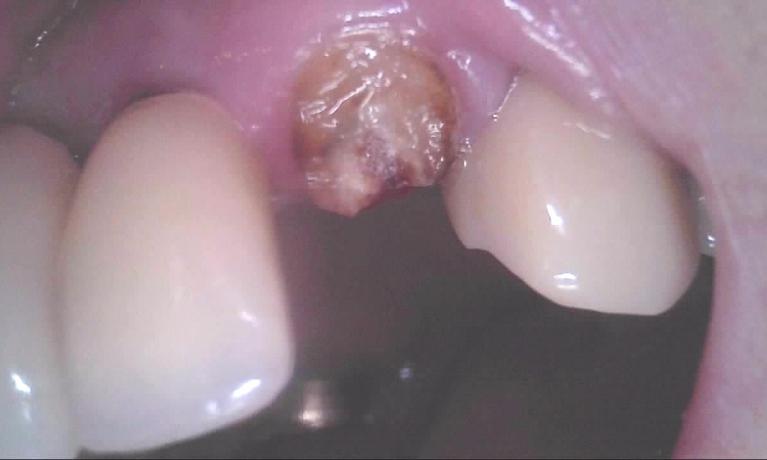

We take great pride in the services we perform in our office. We always try to not only meet your expectations, but we also try to exceed them. There are many types of services that we perform in our office, as well as others that we perform in coordination with highly skilled specialists. We have compiled a few examples of the treatments that we have performed. We are proud to say that these are the usual results our patients expect to see.

The photos are not retouched, nor are they taken by a professional photographer. These are just the routine treatment photos that we take and the results that we see every day. They are by no means a comprehensive catalog of the procedures that we perform. They are just a small sample of some of the results you can expect when you seek treatment in our office.